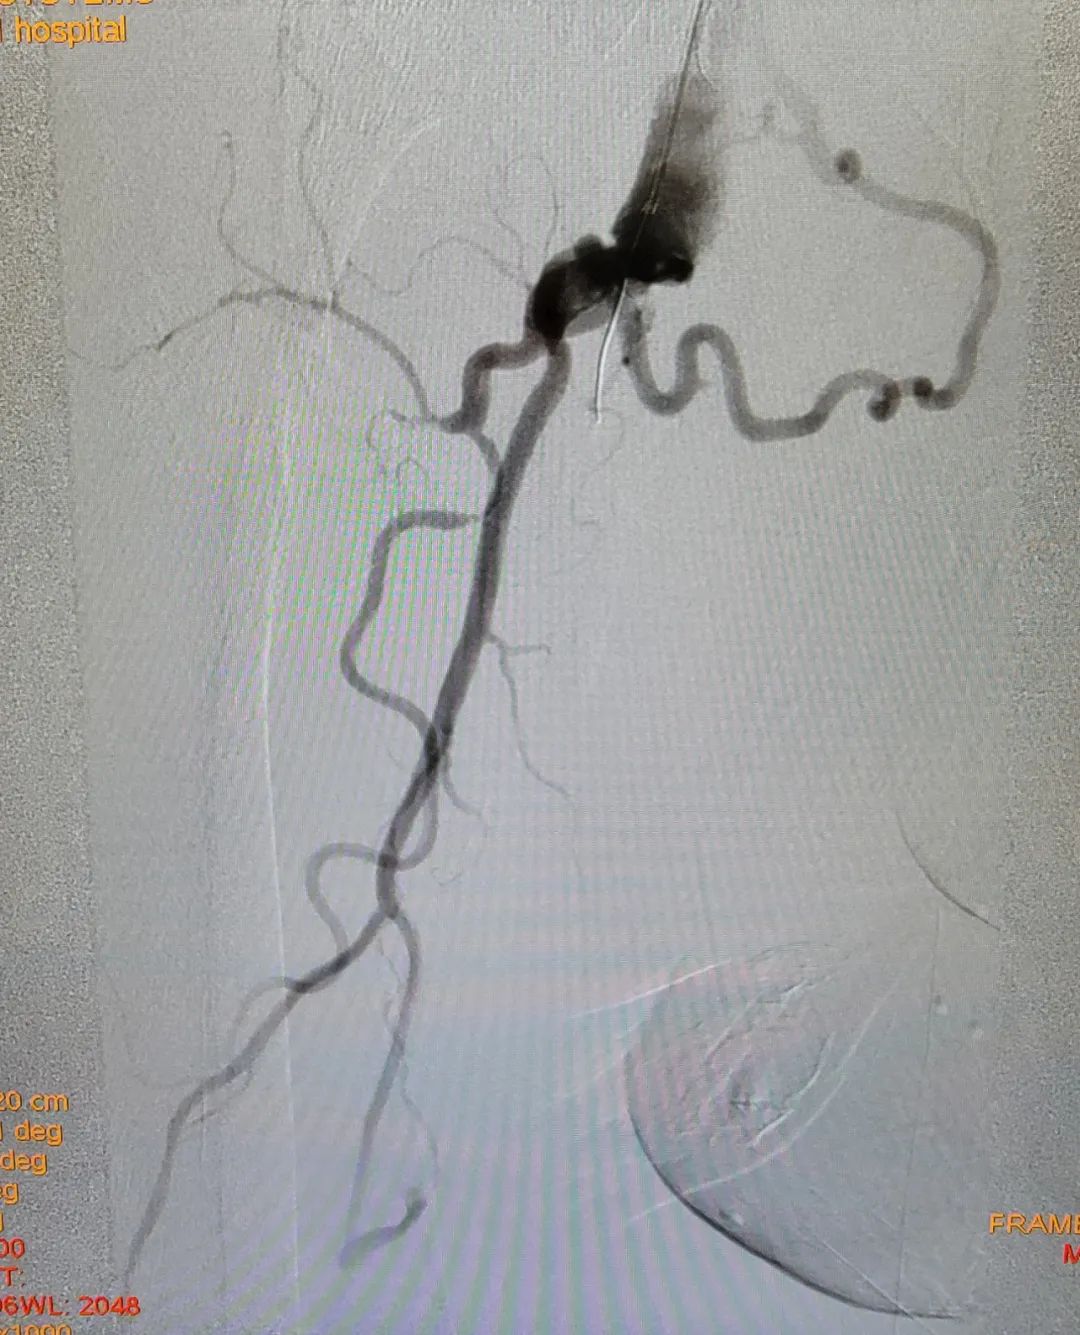

为此,熊小蔚及其团队提出为刘大爷进行分期手术,在镇静、镇痛辅助局麻条件下进行第一期行动脉斑块切除+支架植入的复合手术,重点解决刘大爷静息痛的问题。同时,经过一期手术后的血管代偿机制,刘大爷脚部的溃疡很有可能自愈,这样既满足了刘大爷病情治疗的需求,也最大程度减少了风险的发生。

在经过和刘大爷及其家属的充分沟通后,手术顺利进行,术中既开通了闭塞的双侧髂动脉,同时也保护好了刘大爷原有的侧支血管,最大程度保障了下肢的动脉血流灌注,双足的缺血症状明显改善、坏疽范围得到控制,同时,也没有出现湿性坏疽及感染等情况。经过精心的护理,刘大爷顺利出院了。